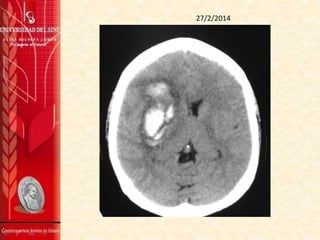

TAC DE CRÁNEO SIN CONTRASTE 27/2/2014

Se aprecia gran hematoma intraparenquimatoso

comprometiendo la región ganglio basal derecha, parte del

lóbulo frontal y temporal del mismo lado, sus contornos son

irregulares y sus diámetros máximos del plano axial son de 59

mm (AP) x 27 mm (TRV). Sus características están a favor de

una etiología hipertensiva entre otros diagnósticos

diferenciales.

La línea media está desviada hacia la izquierda

aproximadamente 6 mm por el efecto de masa producido por

el hematoma, y colapsa casi totalmente el ventrículo lateral

derecho.

No se aprecian alteraciones en la fosa posterior.

IMPRESIÓN:

1. Hematoma intraparenquimatoso comprometiendo la

región ganglio-basal derecha, parte del lóbulo frontal y

temporal del mismo, muy probablemente de origen

hipertensivo.

TAC DE CRÁNEO SIN CONTRASTE 7/3/2014

Se observa una imágen hiperdensa que compromete la

región ganglio-basal derecha, de contornos difuminados, de

aproximadamente 40 mm por 19 mm, en el plano axial con

aspecto de hematoma intraparenquimatoso, sus contornos

hacen pensar en una evolución hacia la cronicidad.

Hay discreto efecto de masa dado por el edema alrededor de

la lesión que está desviando la línea media unos 7 mm a la

izquierda.

No se aprecian masas extra axiales.

La fosa posterior es normal.

1. Hematoma intraparenquimatoso en la la región ganglio-

basal derecha.